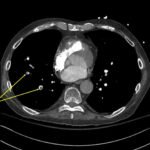

A 78-year-old gentleman presented to the emergency department (ED) for palpitations and dizziness. He had a complicated medical history including atrial fibrillation (AF), recently status post a Watchman procedure, oxygen-dependent chronic obstructive pulmonary disease (COPD), and heart failure with preserved ejection fraction (HFpEF). Point-of-care ultrasound (POCUS) revealed the presence of an intracardiac right atrial thrombus. Computed tomography (CT) angiography confirmed the presence of multiple pulmonary emboli (PE), and extension of the thrombus into the inferior vena cava. Pulmonary emboli are a common complication of thrombus in the right atrium. Management may include anticoagulation, thrombolysis, or thrombectomy. This case highlights that emergency physicians can expedite the diagnosis of intracardiac thrombus by using POCUS. The case presented describes a medically complex patient presenting with symptomatic right intracardiac and inferior vena caval thrombosis complicated by multiple PE. Point-of care ultrasound of the heart and lungs were included in his initial assessment, revealing findings of an intracardiac thrombus, and ruling out multiple other differential diagnoses including pericardial tamponade, pleural effusion, pulmonary edema, and pneumothorax. This finding changed the trajectory of this patient’s evaluation and management, and demonstrates the important role of POCUS in the care of ED patients with undifferentiated cardiopulmonary symptoms.